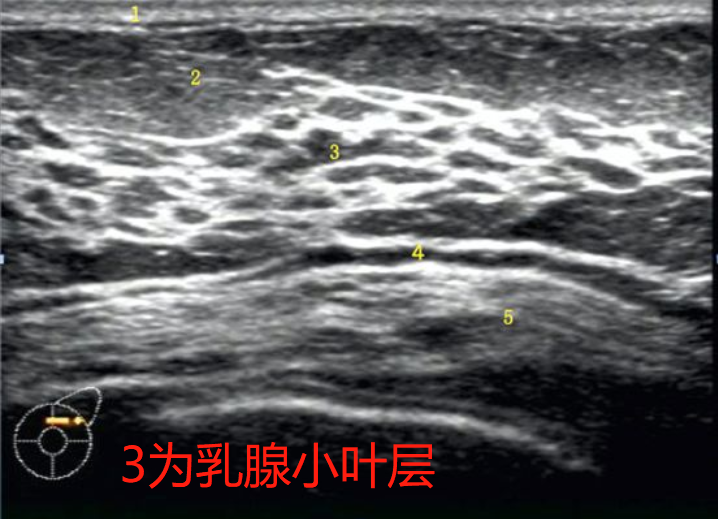

因为乳腺小叶位于乳房,因此乳房位置即乳腺小叶位置。乳房由皮肤、脂肪组织、纤维组织和乳腺构成。乳腺被结缔组织分隔成15-20个乳腺叶,每个乳腺叶又分为若干个乳腺小叶。每个乳腺叶有一排泄管,称为输乳管。当乳腺发生异常时,乳腺小叶可有不同程度的肿大、增生。